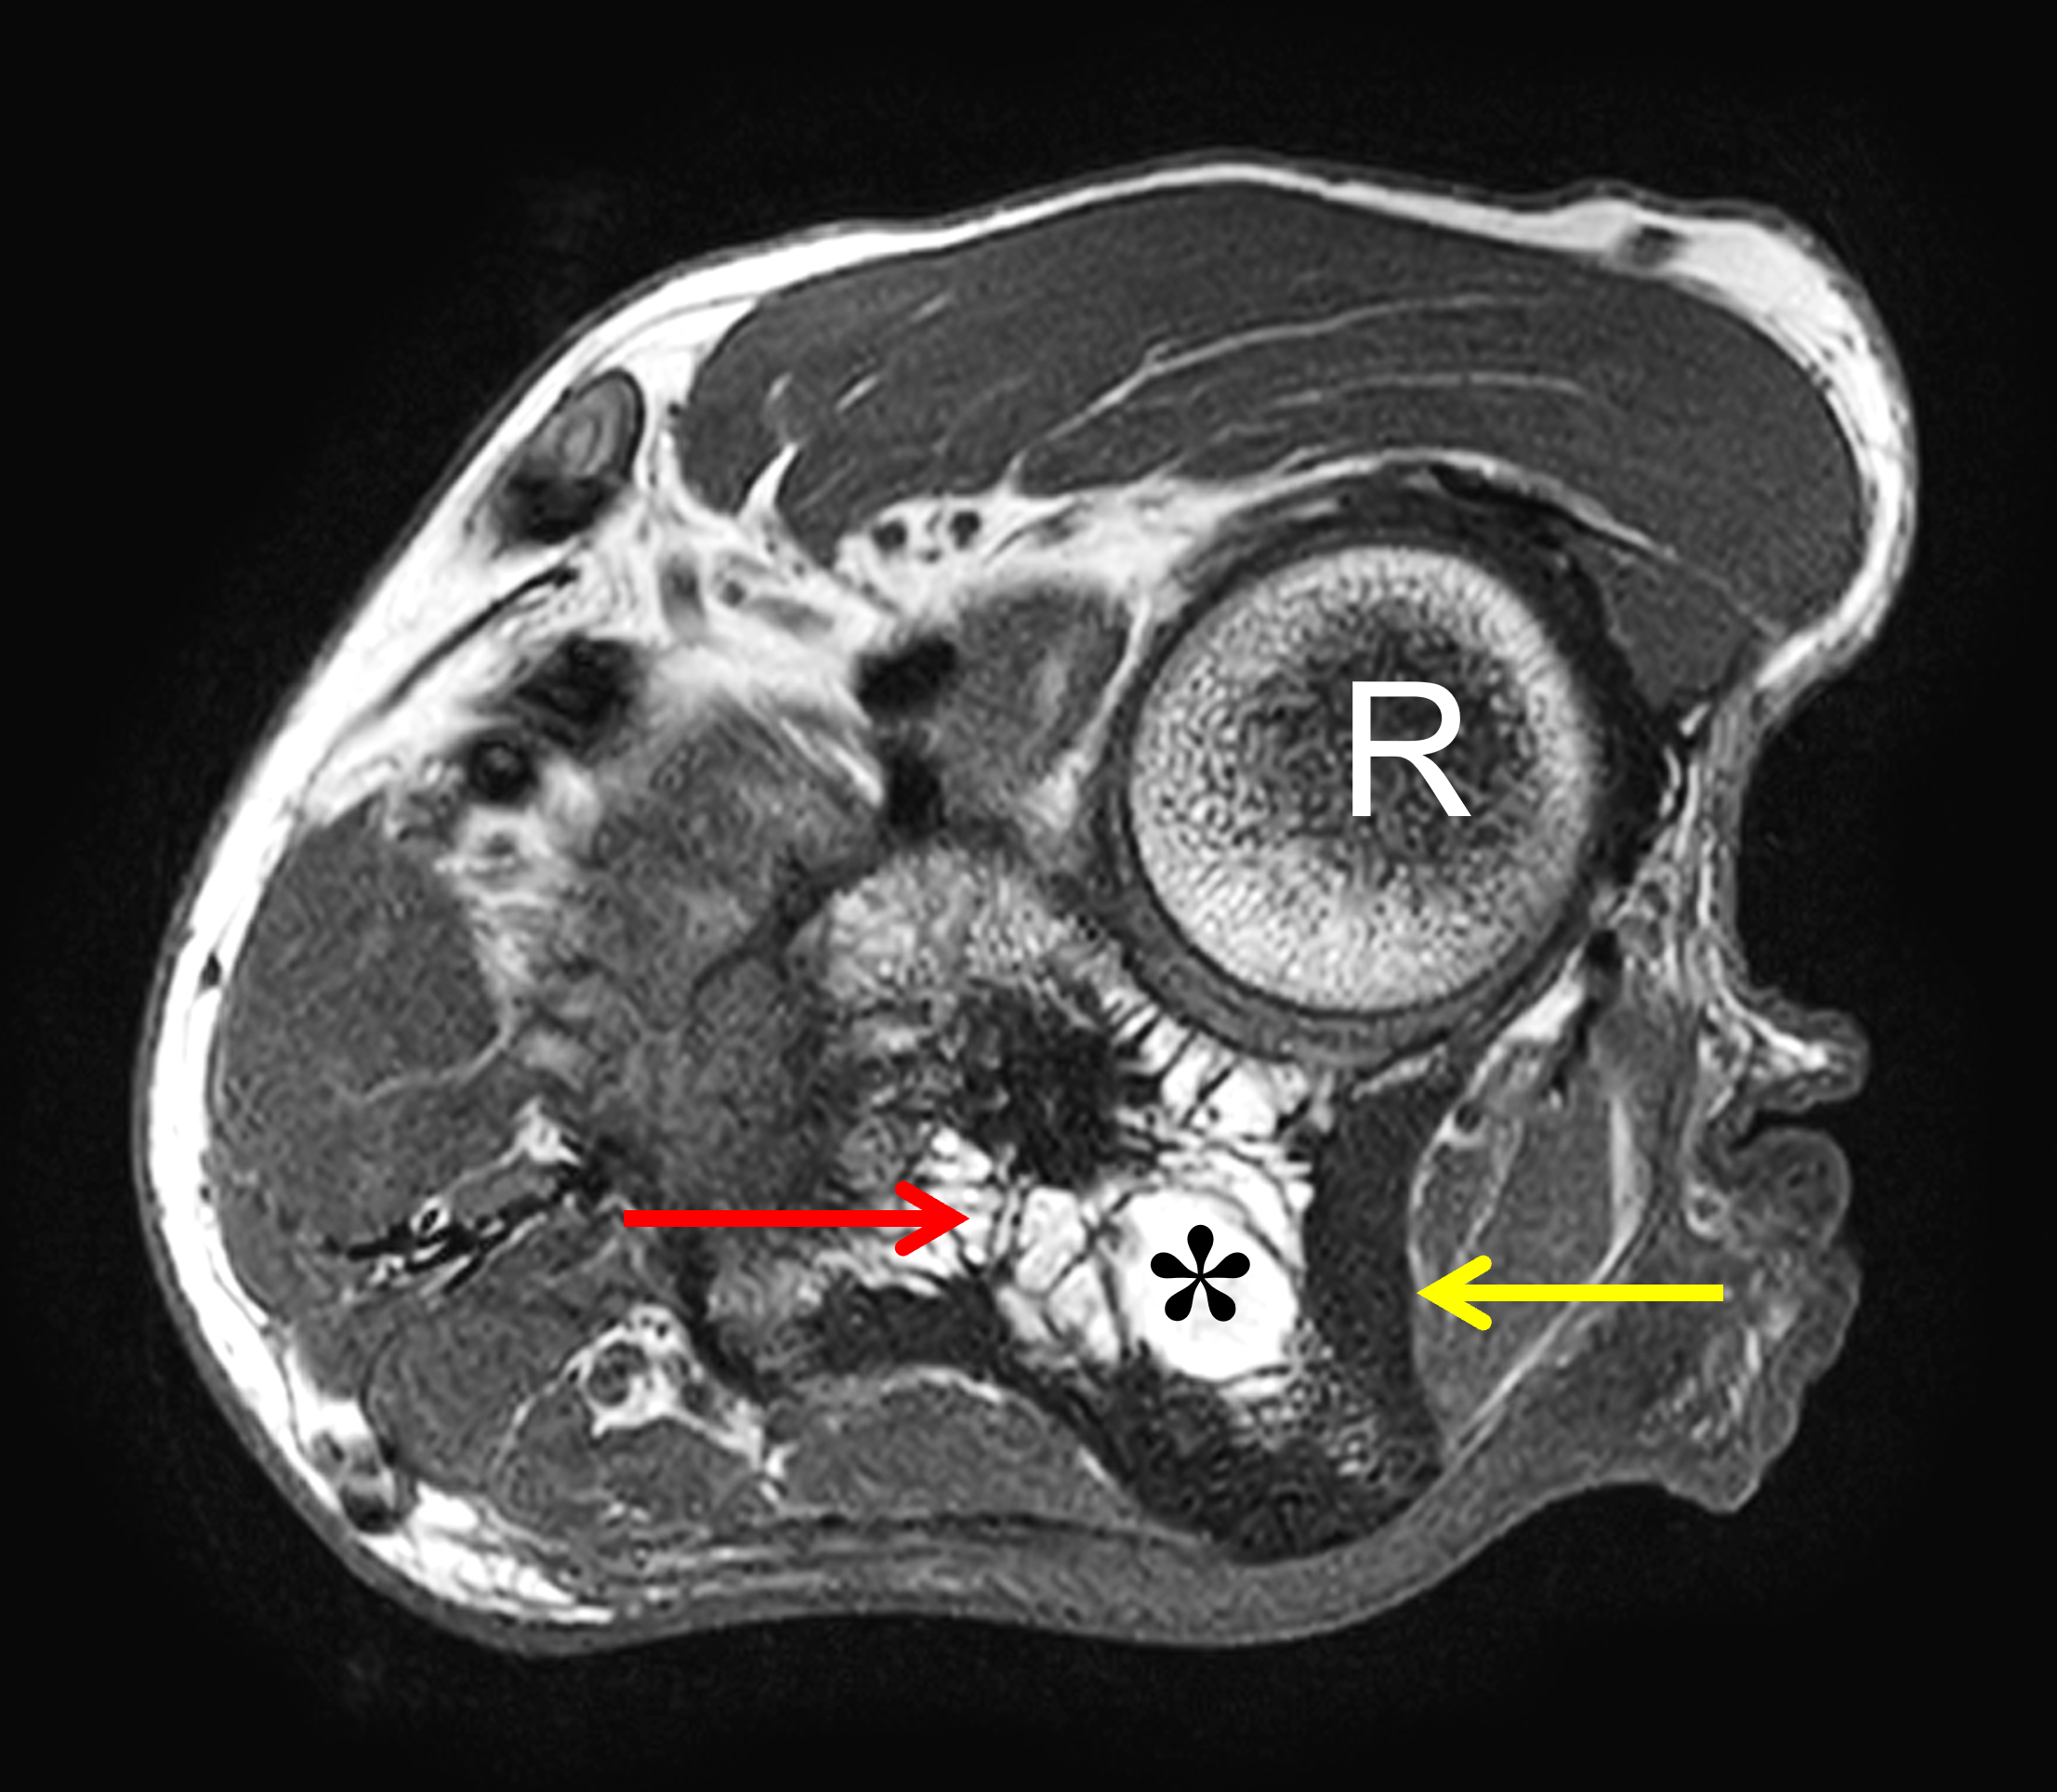

Pattern 1. Fatty marrow is predominantly preserved across pulse sequences (easiest to appreciate on T1-weighted images) corresponding pathologically to atrophic marrow, with associated trabecular coarsening and cortical thickening (Figure 3).26,27 Cortical expansion may narrow the medullary cavity. Post-contrast enhancement, when present, is typically mild and/or patchy. This pattern is most frequently associated with long-standing disease.

Figure 3: Paget disease of the proximal ulna, MRI pattern 1. (3A) Axial and (3B) coronal T1-weighted images show cortical thickening (yellow arrows) and coarse trabeculae (red arrows) in the ulna compared to the radius (R). Note the preserved high signal intensity fat in the bone marrow (asterisks). (3C) Lateral and (3D) AP radiographs show the typical findings of mixed-phase Paget disease of the ulna with bone enlargement, thick cortex, and prominent trabeculae. Bowing of the ulna indicates bone softening.